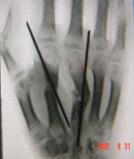

克氏针

一种骨科常用的内固定材料,其原规格一般固定在二十公分左右,直径在0.5-2毫米间有不同的几种规格。用于固定短小骨折或撕脱骨折等应力不大的骨折固定,也常被用在骨科手术中临时骨折块的固定中。近年来随着外固定支架的广泛应用,克氏针的最大直径逐渐曾加到4毫米,配合外固定锁钉来固定骨盆骨折跟骨骨折等应急较大的骨折。